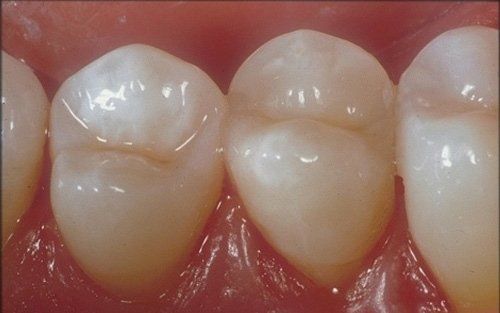

Il dente durante la terapia ricostruttiva: è stata rimossa il vecchio restauro in amalgama e pulita la cavità dalla carie.

La terapia ricostruttiva completata